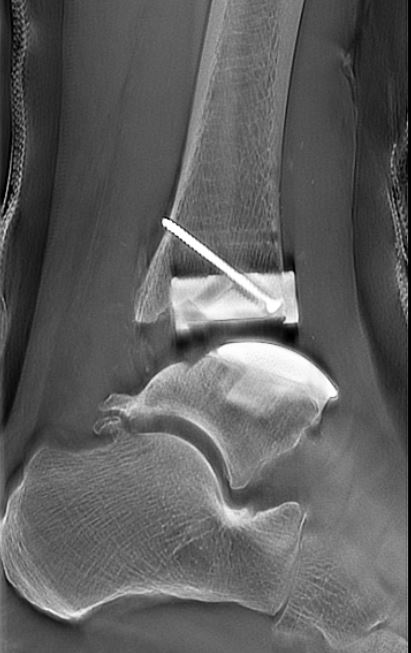

断層撮影は整形の領域でも行います。通常のX線撮影では骨や軟部組織が重なり合って見えにくいことがありますが、断層撮影では、特定の層(断面)だけをクリアに映し出すことができるため、骨や関節のより詳細な評価が可能です。特に、骨折、関節の変形、骨の異常などの診断において有効です。また、立位で検査を行うことも可能です。立位での撮影により、体重が関節や骨に与える影響を観察することができます。

通常のX線画像 |

断層撮影画像 |